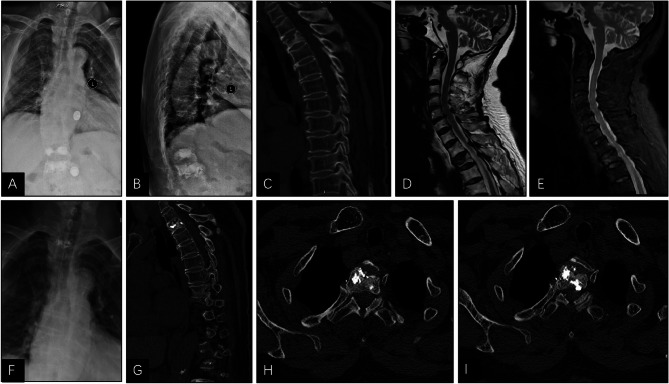

Methods: A retrospective analysis was performed on 62 patients with OVCF of the middle and upper thoracic vertebrae (T1-T8) who underwent PVP surgery in Shenzhen Traditional Chinese Medicine Hospital from January 2017 to January 2023. Of them, 30 and 32 patients underwent TiRobot-assisted PVP surgery (robot group) and conventional C-arm-assisted PVP surgery (conventional group), respectively. VAS and ODI scores and the anterior height and local kyphotic angle of the fractured vertebra were compared before surgery and 3 days, 1 month, and 1 year after surgery. Simultaneously, the operation time, intraoperative blood loss, puncture frequency, fluoroscopy frequency, hospital stay, surgeon radiation exposure, patient radiation exposure, bone cement leakage, cement distribution, and complication were compared between the two groups.

Results: VAS score and ODI score at 3 days, 1 month, and 1 year after surgery were significantly improved in both groups compared with those before surgery (p < 0.05). The VAS score of the robot group was lower than that of the conventional group 3 days after surgery (p < 0.05), with no significant difference observed before and after surgery (p > 0.05). No significant difference was observed in anterior height and local kyphotic angle of fractured vertebra between the two groups before and after the surgery (p > 0.05). The operation time, intraoperative blood loss, puncture frequency, fluoroscopy frequency, hospital stay, surgeon radiation exposure, patient radiation exposure, bone cement leakage, and cement distribution of the robot group were all better than those of the conventional group (p < 0.05). Simultaneously, the incidence of complications in the robot group was 3.33% (1/30) lower than that of the conventional group (15.62%) (5/32) (p < 0.05).